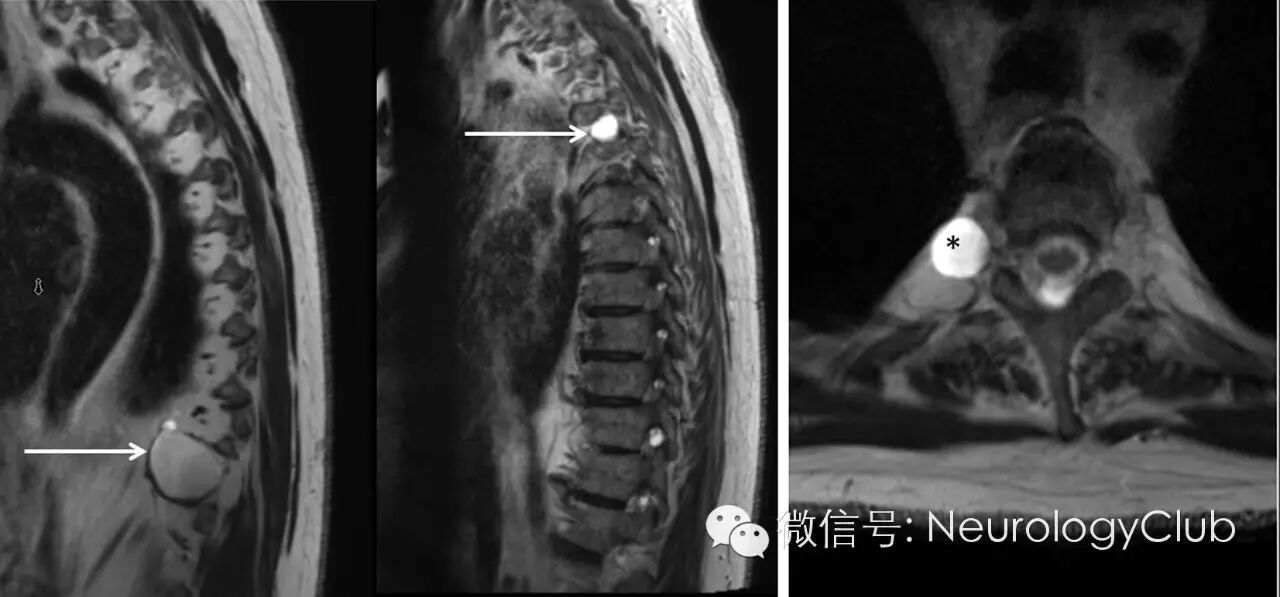

(图1:T1WI[左],T2WI[中]以及增强压脂MRI[右]可见一边界清楚哑铃型病灶[*],大小约3.6×3.7cm,无边缘强化,位于左侧T10-T11椎间孔,导致孔增宽)